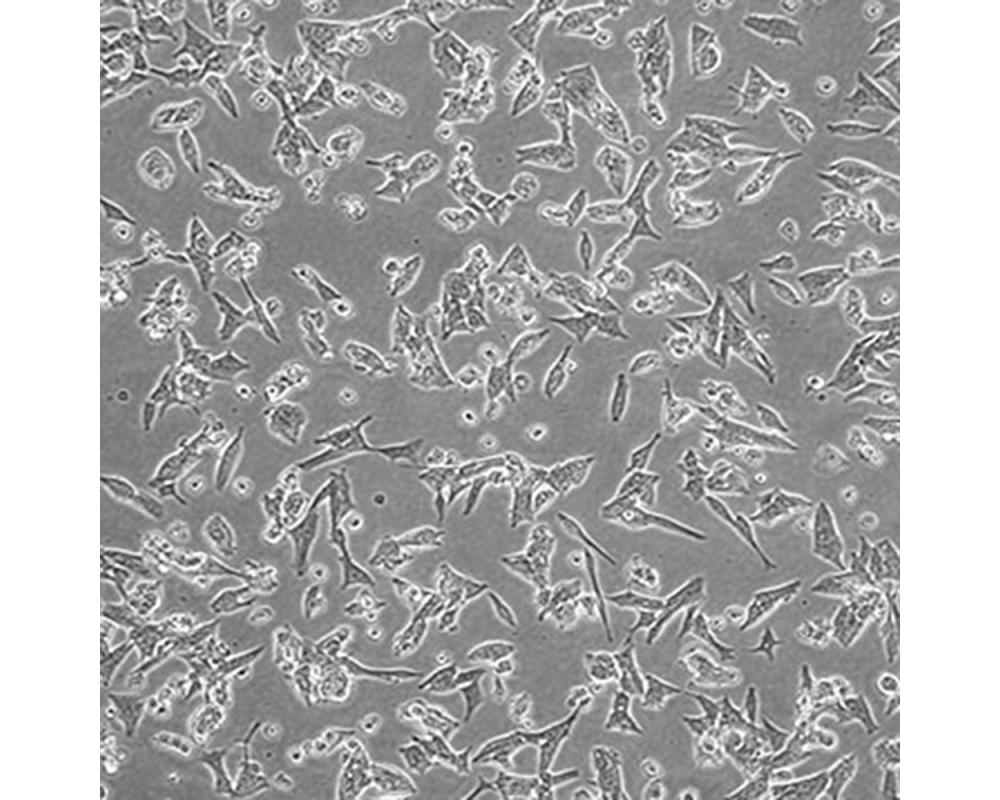

產(chǎn)品名稱 VCaP

中文名稱 人前列腺癌細胞

組織來源 前列腺癌;男性

形態(tài)特征 上皮細胞

生長特性 貼壁生長

特征特性 1997從一位不受激素影響的前列腺癌患者脊椎轉(zhuǎn)移灶中建立了這株細胞。先在小鼠中進行異種移植傳代,隨后進行體外培養(yǎng)。體內(nèi)及體外都對雄性激素敏感。

培養(yǎng)條件 DMEM(高糖)+10%FBS,氣相:空氣,95%;二氧化碳,5%。溫度:37攝氏度。

傳代方法 消化3-5分鐘。1:2。3天內(nèi)可長滿。